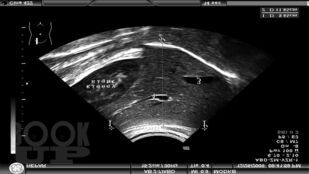

В справочно-практическом руководстве приведены и систематизированы планиметрические (размерные) и количественные показатели внутренних органов при ультразвуковых исследованиях у детей и взрослых. Даны количественные показатели внутрисосудистой гемодинамики артерий различных бассейнов в норме. Представлены количественные и гемодинамические показатели при ультразвуковом исследовании сердца как у детей, так и у взрослых. Эти данные помогут отличить норму от патологии. Приведена оценка степени выраженности клапанных пороков сердца. Изложены методологические основы проведения измеренийпри ультразвуковых исследованиях.

В новое издание включены главы, где предлагаются объективные ультразвуковые критерии при экстренной абдоминальной патологии (острый аппендицит, кишечная инвагинация, гипертрофический пилоростеноз), УЗИ тазобедренных суставов у детей до года. Приведены таблицы для определения срока беременности в первом, втором и третьем триместрах.